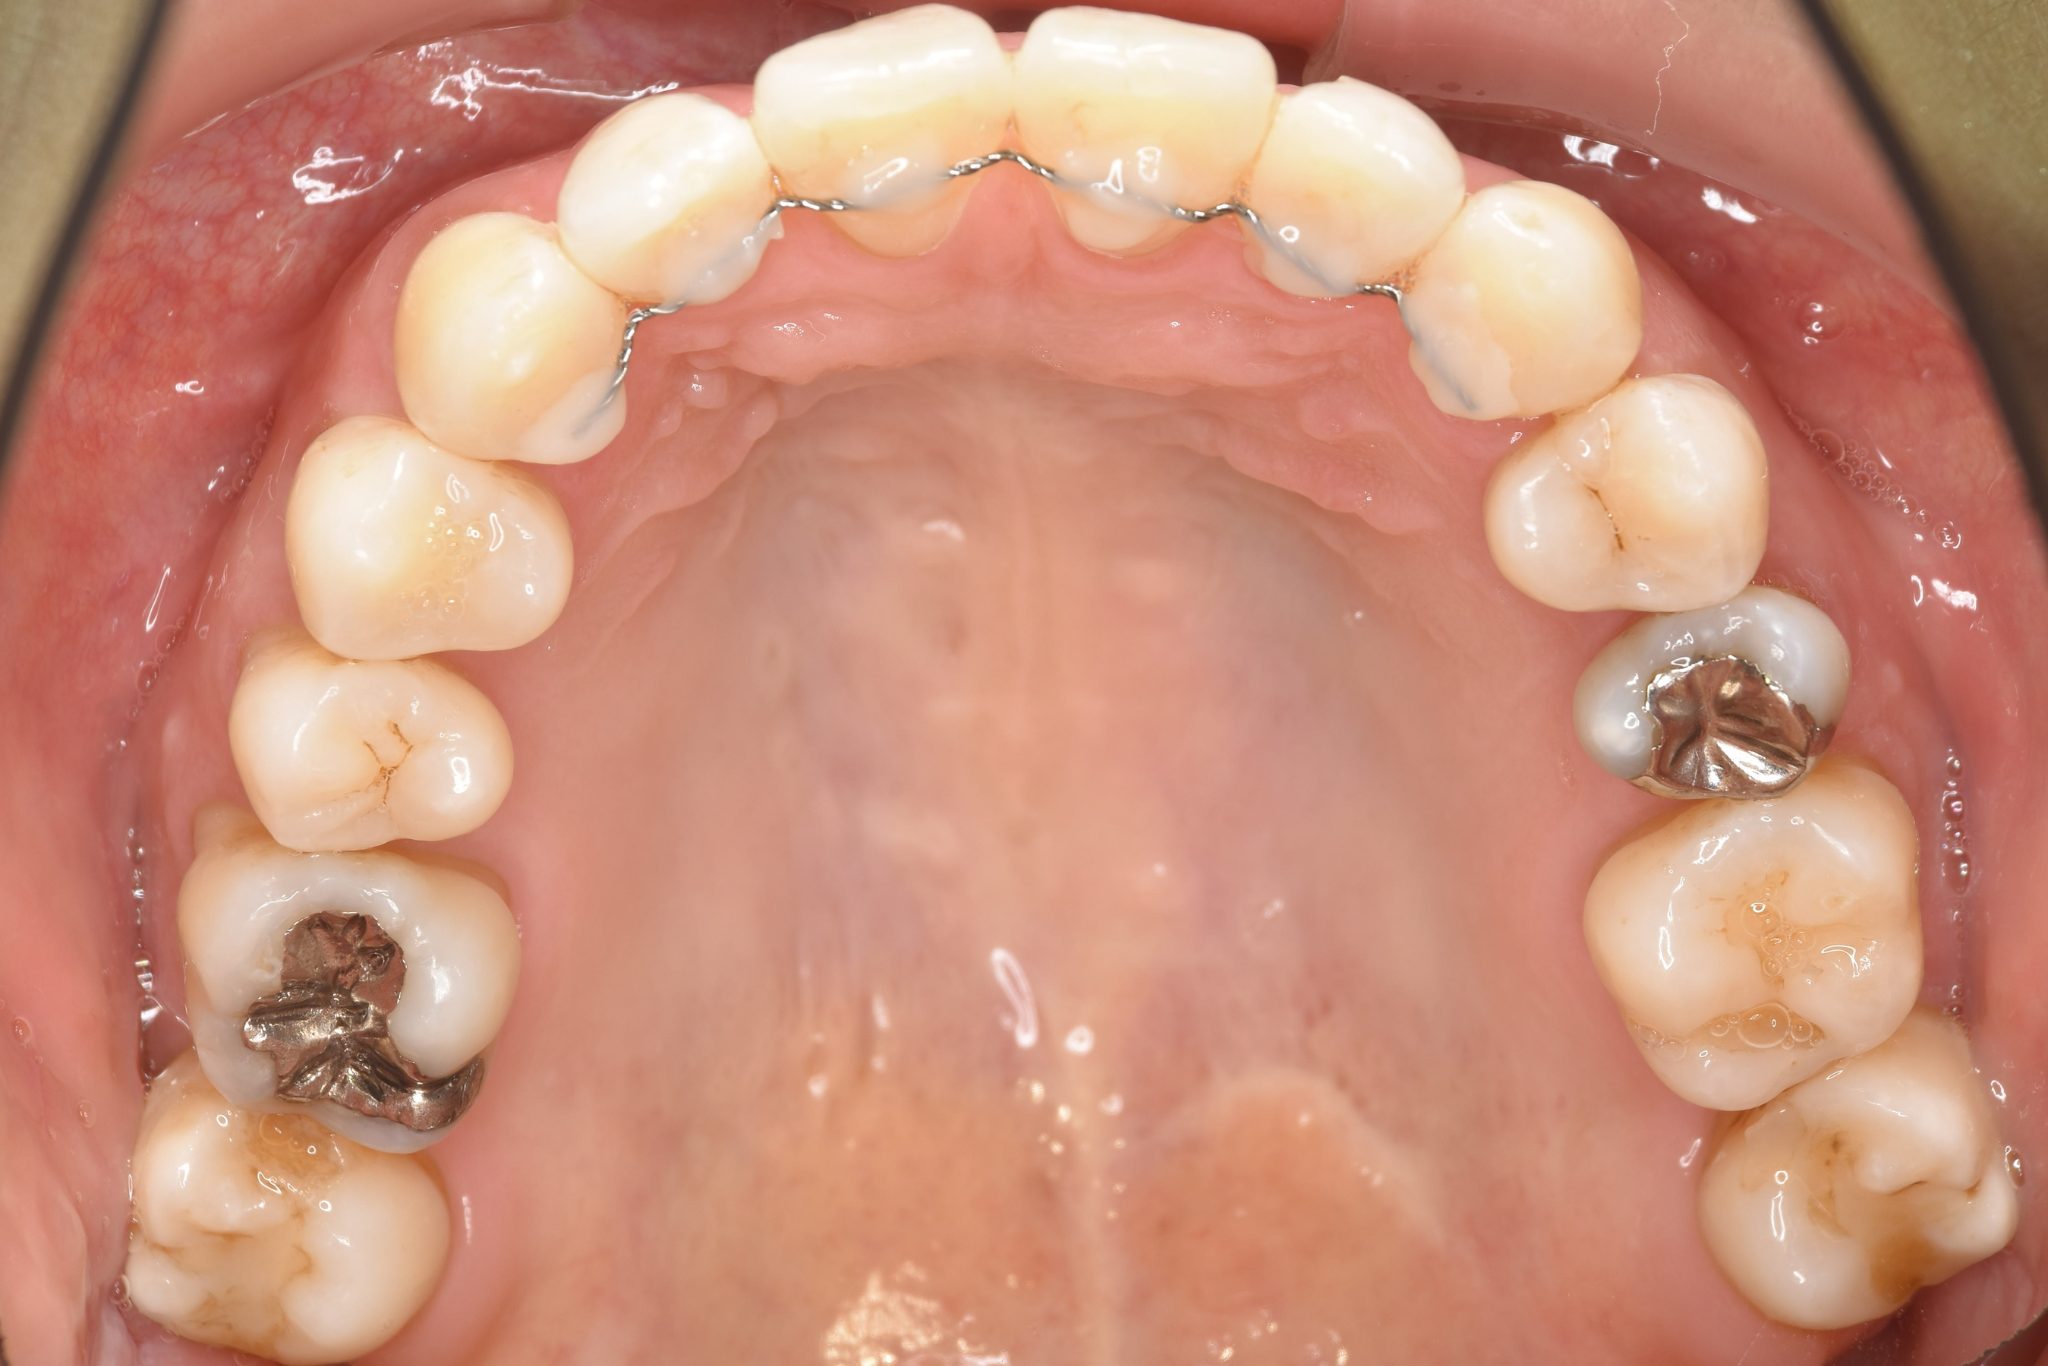

ビフォー

保険での矯正治療|症例_138

主訴 噛み合わせが悪い(反対)|歯並びが悪い|顎が出ている

施術内容 マルチブラケット装置を用いて歯牙を配列した後、

下顎骨離断術を行った。良好な咬合を獲得した。

治癒期間 3年8ヶ月間

費用 保険治療

リスク・副作用 違和感、不快感、痛み